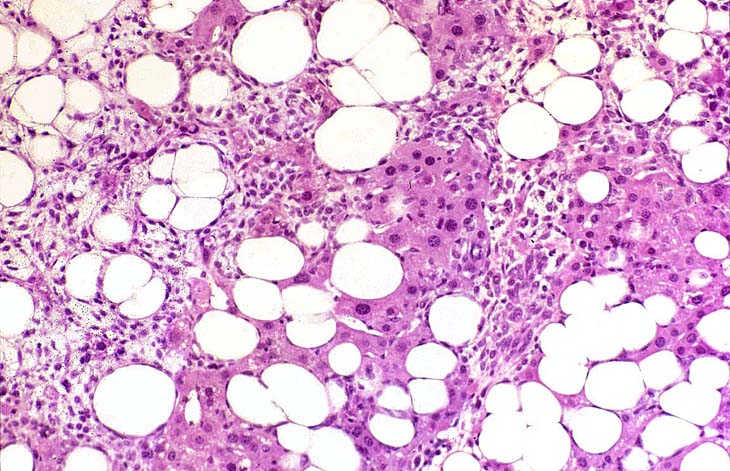

This Ito cell tumor is comprised of a mixture of stellate cells and mature adipocytes.